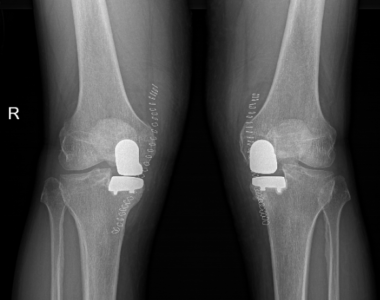

La protesi del ginocchio, totale o parziale (monocompartimentale o bicompartimentale), è uno degli interventi ortopedici più frequentemente eseguito in tutto il mondo, insieme alla protesi dell’anca. In una percentuale di circa il 30% dei casi l’artrosi del ginocchio colpisce entrambe le articolazioni, generalmente in misura diversa, nel senso che c’è sempre un ginocchio più danneggiato e più dolorante, anche se a volte a maggior usura non corrisponde maggior dolore.

Ma ovviamente non tutti i pazienti possono affrontare un intervento bilaterale simultaneo (soprattutto se si tratta di una protesi totale bilaterale del ginocchio). I rischi da prendere in considerazione sono legati soprattutto alle perdite ematiche. I pazienti anemici, cardiopatici e con un rischio anestesiologico alto non possono essere candidati a questo tipo di chirurgia.